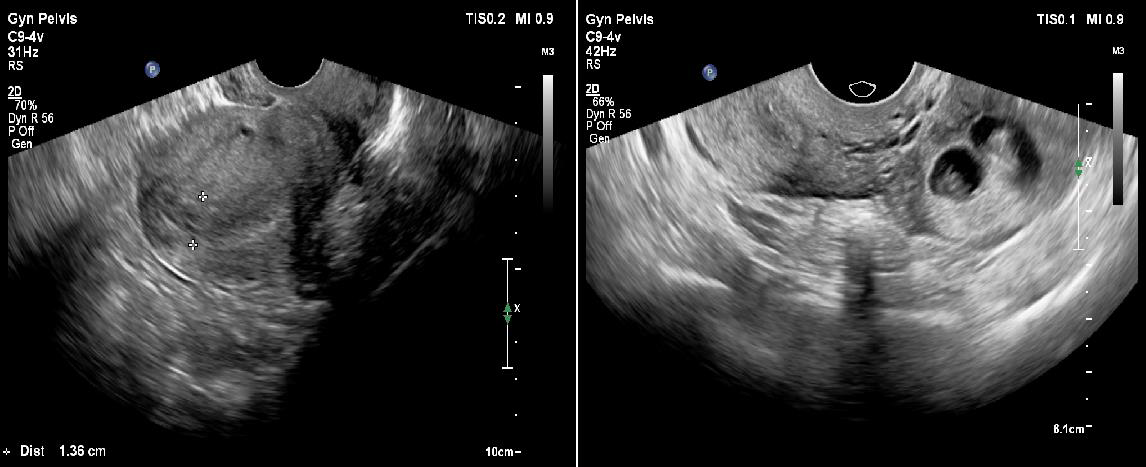

Transabdominal ultrasound revealed a bulky uterus with a thickened endometrium; however, no intrauterine gestational sac was appreciable. A thick-walled cystic structure was noted in the left adnexa with only one fetal pole initially visualized. [Figure 1a and 1b]. Subsequently performed transvaginal ultrasound revealed two gestational sacs in the left adnexa. Twin peak sign was identified, which confirmed dichorionicity. Each gestational sac contained a fetal pole-yolk sac complex [Figure 2a]. Cardiac activity was present in both embryos, confirmed on color Doppler study [Figure 2b]. Crown rump lengths of twin 1 and twin 2 were 13.3 mm and 14.1 mm, respectively, both corresponding to a gestational age of 7.5 weeks each. [Figure 3a and 3b].

Figure 1: a)-Transvaginal ultrasound image of the uterus with thickened ET.

No intrauterine gestational sac was noted.

b)-Transvaginal ultrasound image depicting the extrauterine location of the two gestational sacs in the left adnexa.